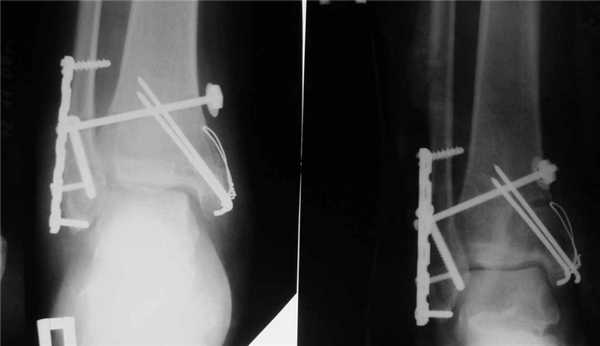

- Открытая репозиция с фиксацией погружными конструкциями. Таким путем лечат все открытые и часть закрытых переломов. В некоторых случаях после операции сустав дополнительно фиксируют гипсом.

Открытая репозиция с внутренней фиксацией

Метод применяют для лечения сложных переломов, когда невозможна ручная репозиция отломков и удержание их в нужной позиции с помощью гипса. Чтобы сопоставить костные фрагменты и надежно зафиксировать их, используют погружные элементы и конструкции:

- болты-стяжки;

- винты;

- болты с клеммами-накладками;

- спицы Киршнера;

- болты с гибкой тягой;

- лавсановые ленты и прочее.

Открытая репозиция обеспечивает одномоментное точное сопоставление отломков и их надежную фиксацию. После операции нередко сохраняется ранняя опороспособность конечности, что позволяет нагружать ее вскоре после операции. И тем не менее многие специалисты уверены, что ни один из методов открытой репозиции не может обеспечить полной неподвижности костных фрагментов. Поэтому после операции пациентам требуется дополнительная гипсовая иммобилизация.